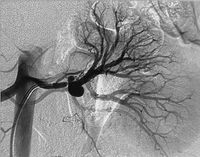

肾动脉造影为最可靠的检查方法,可直接显示动脉壁的囊状膨出或梭形扩张,单发或多发,可大可小,部分有动静脉瘘时,可见肾静脉早显,供血动脉有代偿性增粗并扭曲。